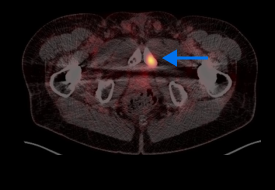

High-risk patient with newly diagnosed prostate cancer

Age

72

PSA (ng/mL)

5.1

Gleason Score

4 + 4

PYLARIFY prompted treatment change from prostatectomy to systemic therapy, thereby avoiding undertreatment